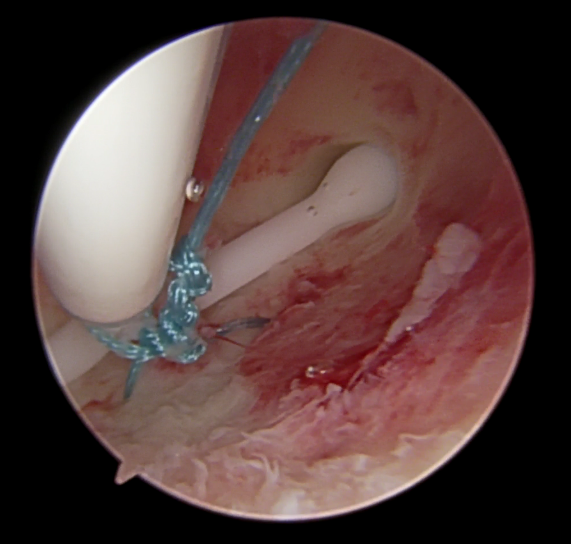

打结

大口径冷刀器械可在直视下采用推结器推结,成功率较高且不容易断线。7Fr/5Fr器械可自制推结器,在曼月乐环推进杆靠近顶端右侧用线剪剪一个倒三角形小洞,打单结后,穿过小洞,用推结器推结,当手感推结器已经到宫底且曼月乐环推进杆标尺已到宫颈外口处时提示打结到位,建议宫腔镜探查打结是否牢靠,必要时可以用勺型钳调结将结收紧,退镜时需注意2根缝线是否平行,谨防打结在中间(图8)

prolene缝线 打结时为什么要喷水曼月乐环总掉?缝合固定术的“10个关键技巧”全公开!从缝线选针到打结,手把手教学_https://www.jmylbn.com_新闻资讯_第8张

图8

因宫腔镜下推结多为滑结,打单结个数以6为宜